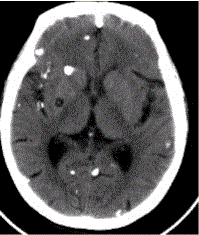

患者男,45岁。头痛、癫痫10余年。查体:无发热,双侧肢体肌力正常。脑电图示双侧额颞叶棘波放电。CT表现如下图。头颅CT检查中,可见囊虫头节钙化,...

问题 患者男,45岁。头痛、癫痫10余年。查体:无发热,双侧肢体肌力正常。脑电图示双侧额颞叶棘波放电。CT表现如下图。 头颅CT检查中,可见囊虫头节钙化,其分期是

选项 A.囊胞期 B.胶样囊胞期 C.肉芽肿结节期 D.结节钙化期 E.脑膜型 F.脑实质型

答案 D